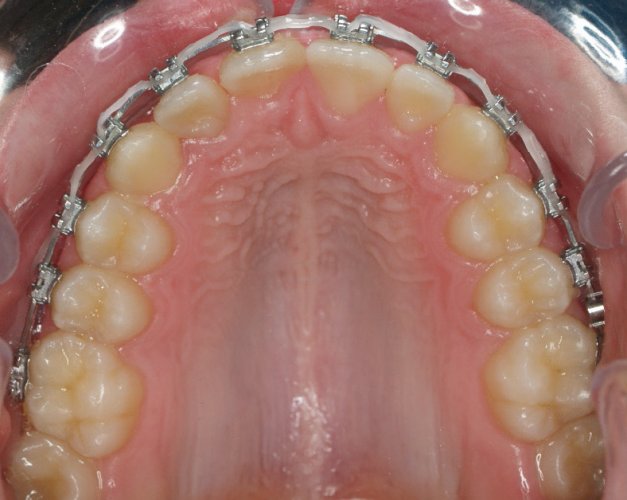

Un “diastema” es una separación extraordinariamente grande entre dos o más dientes. La mayoría de las veces, el diastema aparece entre los dos dientes delanteros superiores. Muchos niños tienen diastema cuando se les caen los dientes de leche, pero en la mayoría de los casos esta distancia desaparece cuando salen los dientes permanentes.

Los diastemas pueden deberse a una diferencia en los tamaños de los dientes, a la falta de algún diente o a que el frenillo labial sea demasiado grande. El frenillo labial es el tejido que va desde el interior del labio hasta la encía, en el lugar donde se sitúan los dos dientes delanteros superiores. Los diastemas también pueden deberse a problemas en la alineación de la boca, como la sobremordida horizontal o la protrusión de los dientes1.

- Realizar un tratamiento ortodóncico para mover los dientes y cerrar el diastema.

Si su frenillo labial es demasiado grande, puede que le remitan a un especialista para someterse a un procedimiento quirúrgico llamado frenectomía. Este procedimiento consiste en cortar el frenillo y volverlo a colocar para permitir que tenga más flexibilidad. Cuando la frenectomía se realiza en un niño, el espacio puede llegar a cerrarse por sí solo. Si se trata de un adolescente o un adulto, puede que sea necesario cerrarlo con ortodoncia. Es esencial acudir al dentista para saber cuál de estas opciones es la adecuada en su caso.